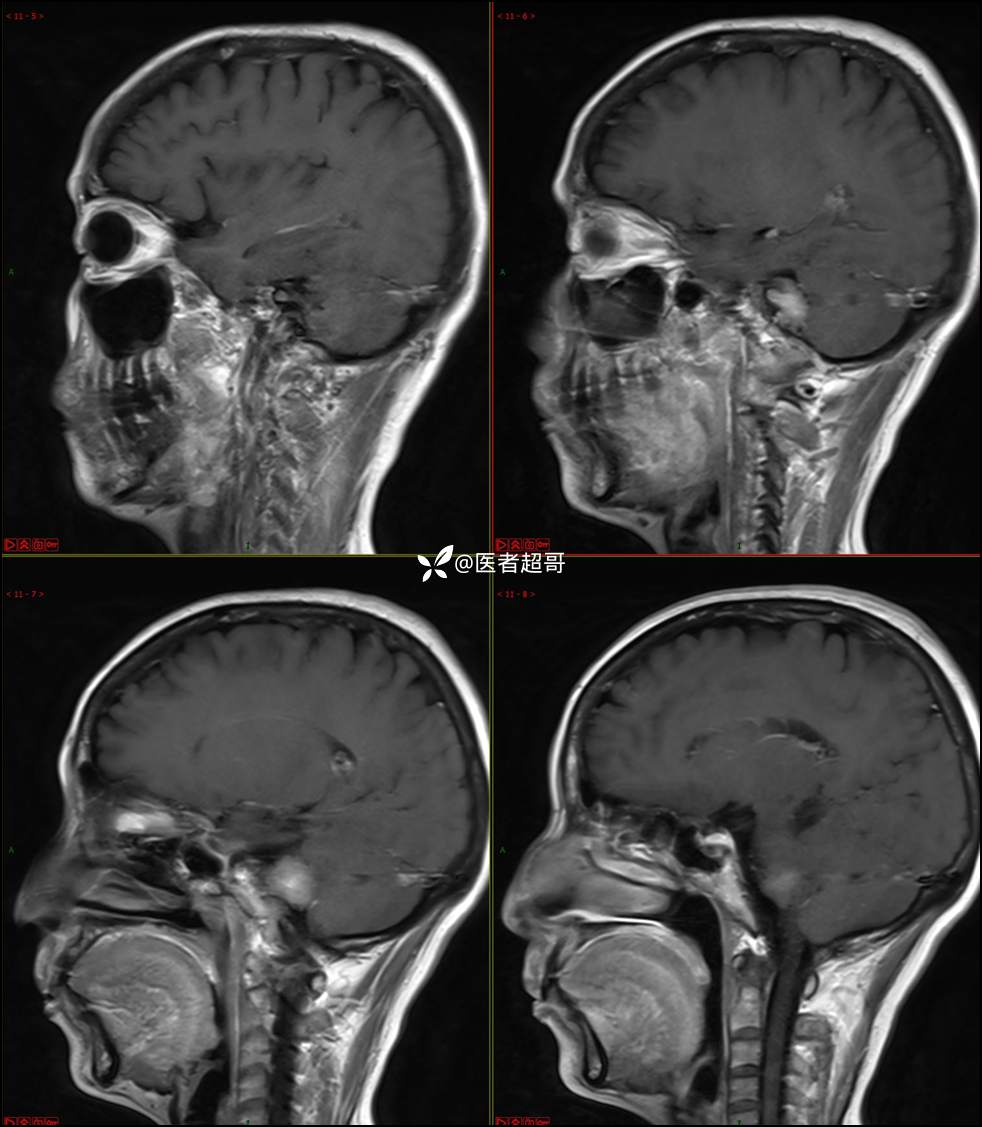

CPA区占位,是鞘瘤?脑膜瘤?请赏析!

主 诉:耳鸣3年,头晕伴恶心4天。

现病史:患者3年前出现耳鸣,蝉鸣音,反复发作,夜间自觉明显,于2018年8月至我院耳鼻喉科就诊,行颅脑CT检查未发现明显异常改变,给予对症处理(具体不详);4天前突发头晕,伴明显恶心,至市人民医院就诊,行颅脑CT未见明显异常,颅脑MRI发现右侧桥脑小脑角区占位性病变。本次发病来无明显头痛,无肢体抽动,无大小便失禁。为求进一步诊治,遂来我院门诊,以“听神经良性肿瘤”收住入院。发病来,患者神志清,精神可,二便正常,饮食可,睡眠不佳,近期体重无明显变化,否认癫痫发作病史。